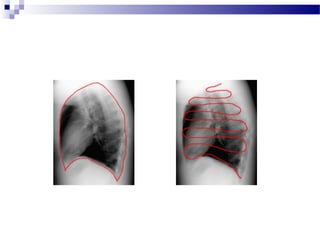

REVĂRSATUL PLEURAL

Cauzele obi nuite de revărsat pleural sunt:ș

- insuficien ă cardiacă congestică;ț

- infec ii (parapneumonice);ț

- traumatisme;

- tumori;

- boli autoimune;

- insuficien ă renală.ț

- Pe o radiografie cu pacientul în pozi ie verticală, un revărsat vaț

cauza rotunjirea laterala a sinusului costofrenic, iar dacă este în

cantitate mare se extinde si posterior;

- Uneori, are loc o depresiune a hemidiafragmului implicat;

- Pentru a detecta un revărsat este necesar aproximativ 200ml de fluid

pe radiografia de inciden a PA i aproximativ 75ml fluid pe cea deț ș

profil;

- Revărsatele mari, în special cele unilaterale, sunt mult mai probabil

cauzate de un proces malign decât cele mici.

- Pe radiografia executata in pozitie dorsală, un revărsat pleural va apărea

ca o opacitate gradată, mai densa catre bază. Vasele pot fi văzute de obicei

prin opacitatea revărsatului pleural. De asemenea, revărsatul pleural

poate acoperi esutul pulmonar, îngro a scizurile, iar daca este inț ș

cantitate mare poate acoperi cu lichid apexul.

- O radiografie realizata in decubit lateral poate fi utilă pentru a confirma

un revarsat pleural la pacientii intui i la pat, lichidul acumulându-se deț ț

partea afectată (cu excep ia pleureziei inchistate).ț